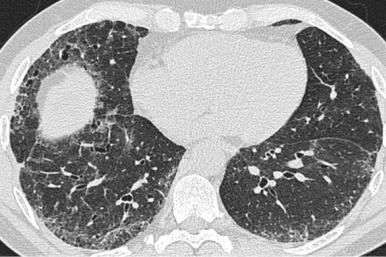

Криобиопсия: техника

Криобиопсия: образцы